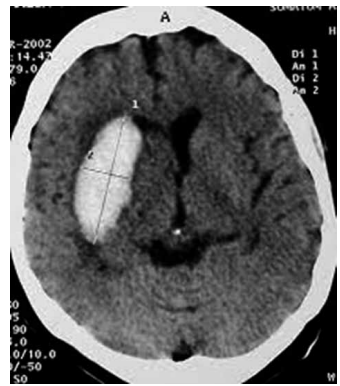

Homem de 67 anos, hipertenso de longa data e sem

acompanhamento médico regular, dá entrada no pronto-socorro com déficit motor súbito à esquerda, cefaleia

intensa e rebaixamento do nível de consciência. A tomografia computadorizada de crânio, encontra-se a seguir.

Qual das seguintes condutas é a mais apropriada nesse caso?